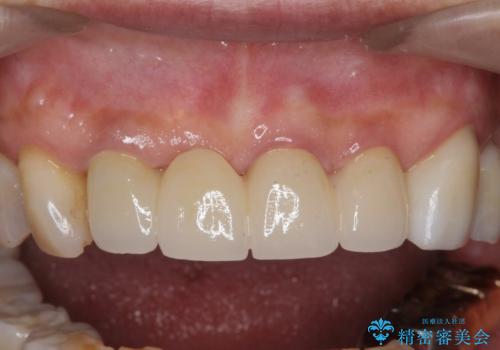

3. ぐらつく前歯 ブリッジ治療の治療後